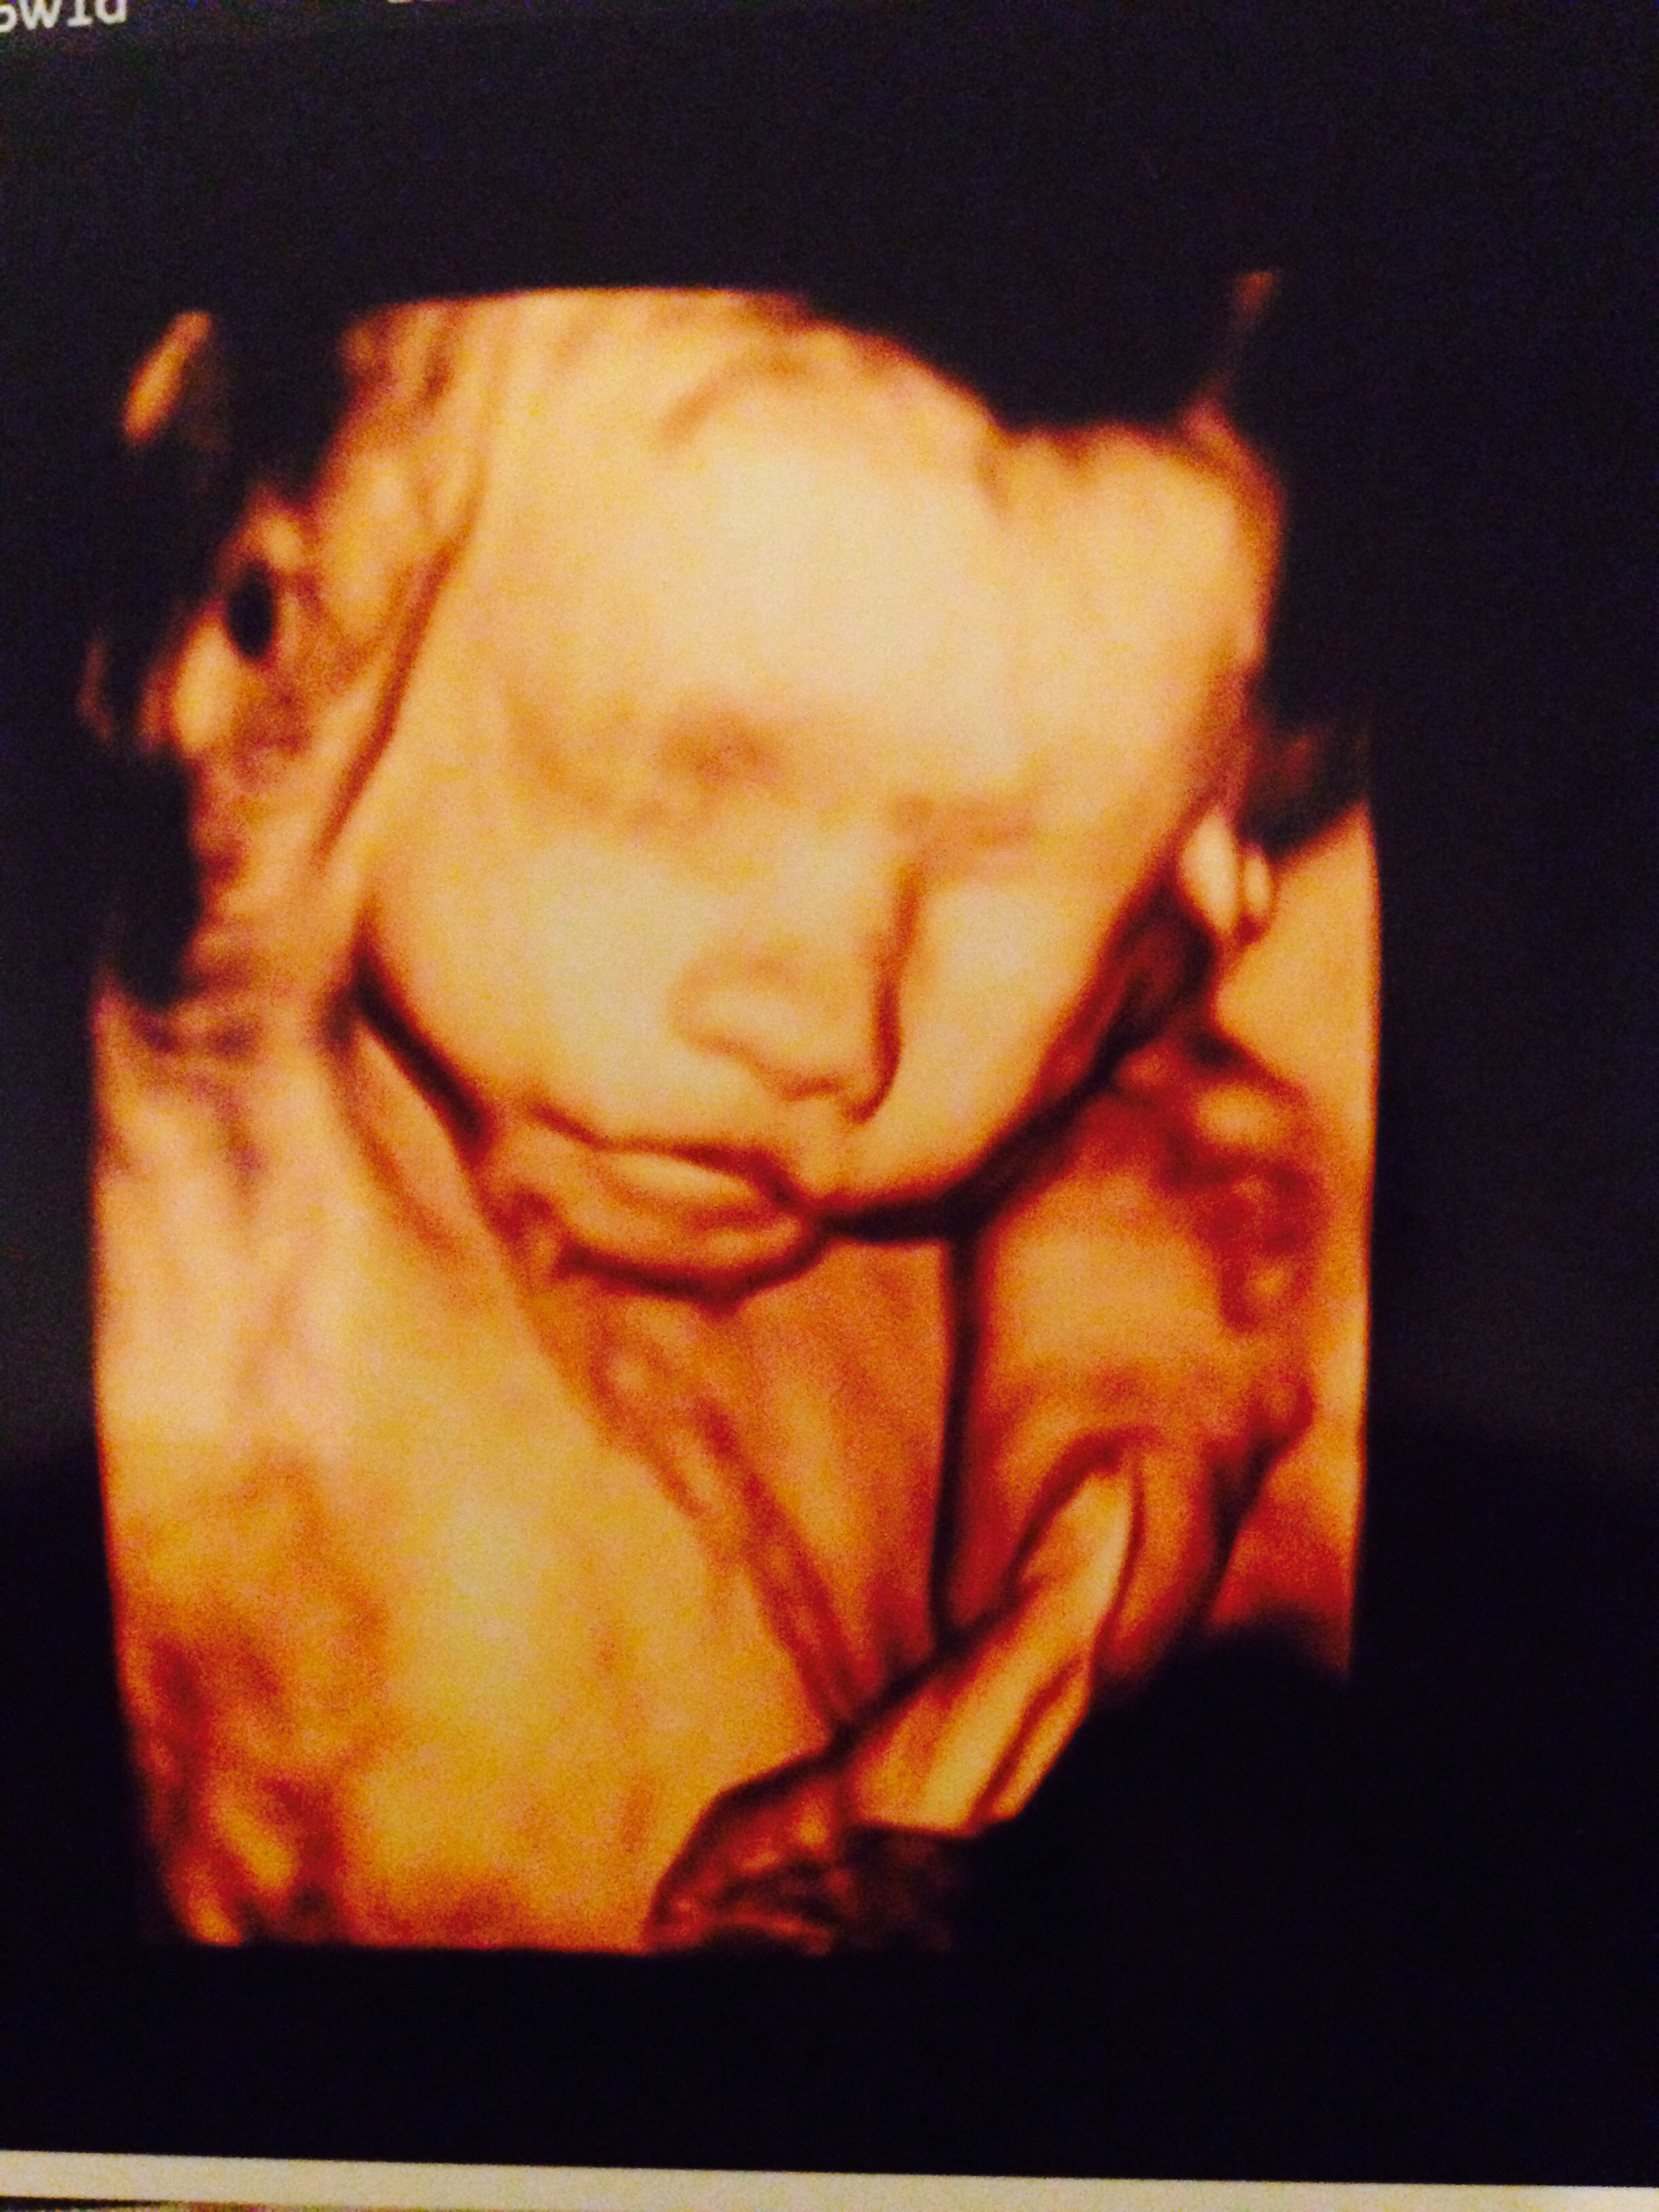

We went for our 4D Ultrasound this weekend and I was so excited to finally get a glimpse at my little one. I am low-risk and my insurance only covers 2 ultrasounds so I haven't seen my little one since 20 weeks (and I'm 30 weeks now). So we loaded up and drove a little ways (as there are not an elective Ultrasound places near us). The whole way down to the place my belly is moving and grooving and turning and as soon as we get there...nothing. He had his hands and feet in front of his face. We did see that we will definitely be having a BOY!!! The tech tried jiggling my belly, filling my bladder, emptying my bladder, I drank ice cold water, juice and ate some candy...he slept through the whole thing. We do get to go back this weekend to try again but I was a little disappointed. Luckily he will be here sooner than later.